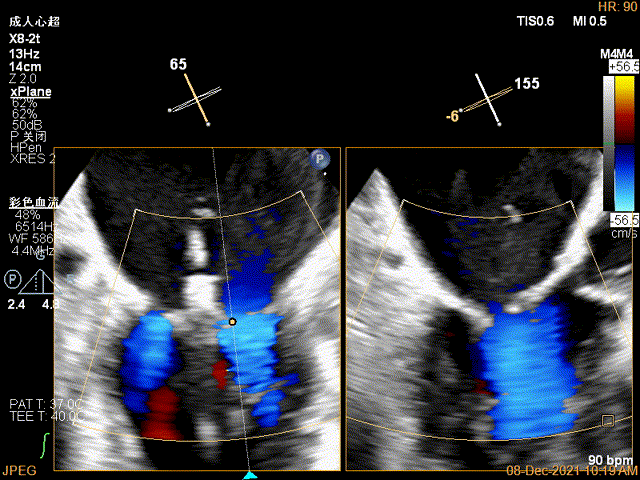

X-plane:下夹子尝试先捕获2区瓣叶

夹子关闭过程中,Color提示2区反流逐渐减少,残余反流位于夹子外侧